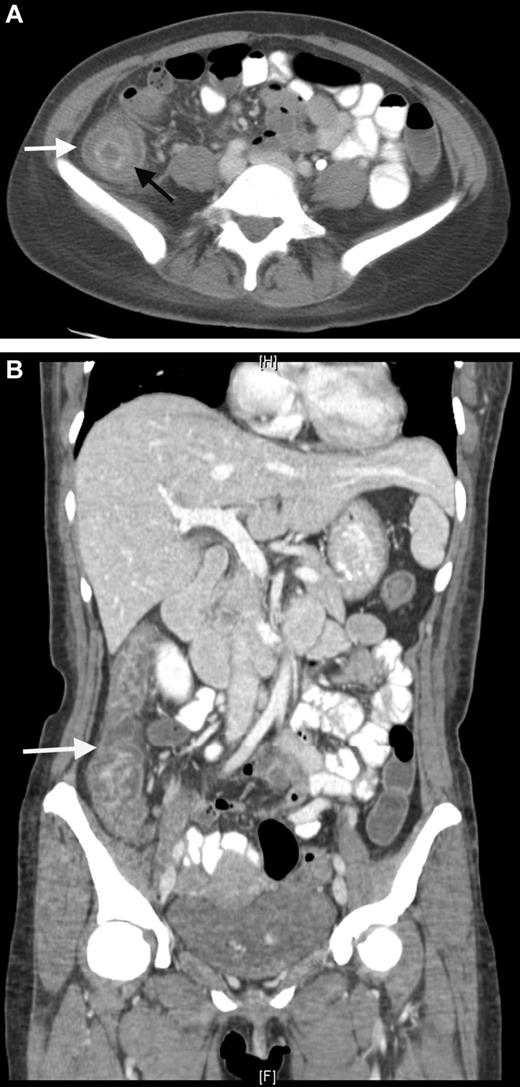

The pathogenesis of NE is linked to the damaged gastrointestinal mucosa. This is attributable to chemotherapy and neutropenia leading to intestinal dysfunction and microbial invasion with, secondarily, edema, inflammation, ulceration, transmural necrosis, and possible perforation.81,84 Abdominal CT (Figure 3) or ultrasound (US) discloses thickening of the bowel wall and intramural edema, which may be accompanied by paracolonic fluid, free air, or pneumatosis intestinalis. A more than or equal to 10-mm wall thickening was associated with 60% mortality compared with 4.2% with less thickening.85 Most authors agree that bowel thickening more than 4 mm is a mandatory criterion for establishing the diagnosis of NE.80 CT imaging is also important to rule out other possible diagnoses, such as appendicitis, diverticulitis, and ischemic colitis. Bowel rest, fluid resuscitation, nasogastric suction, parenteral nutrition, and early surgical consultation are the mainstay of treatment, together with broad-spectrum antibiotics.86

CT scan. Neutropenic enterocolitis. (A) Coronal contrast-enhanced CT image through the abdomen and pelvis. Coronal contrast-enhanced CT demonstrates bowel wall thickening with low attenuation in the submucosal layer of the bowel wall representing bowel wall edema. (B) Axial contrast-enhanced CT through the abdomen. Axial contrast-enhanced CT through the abdomen demonstrates bowel wall thickening with a “target sign” in the ascending colon. The mucosa and muscularis layers are hyperenhancing, whereas the submucosal low density represents bowel wall edema.